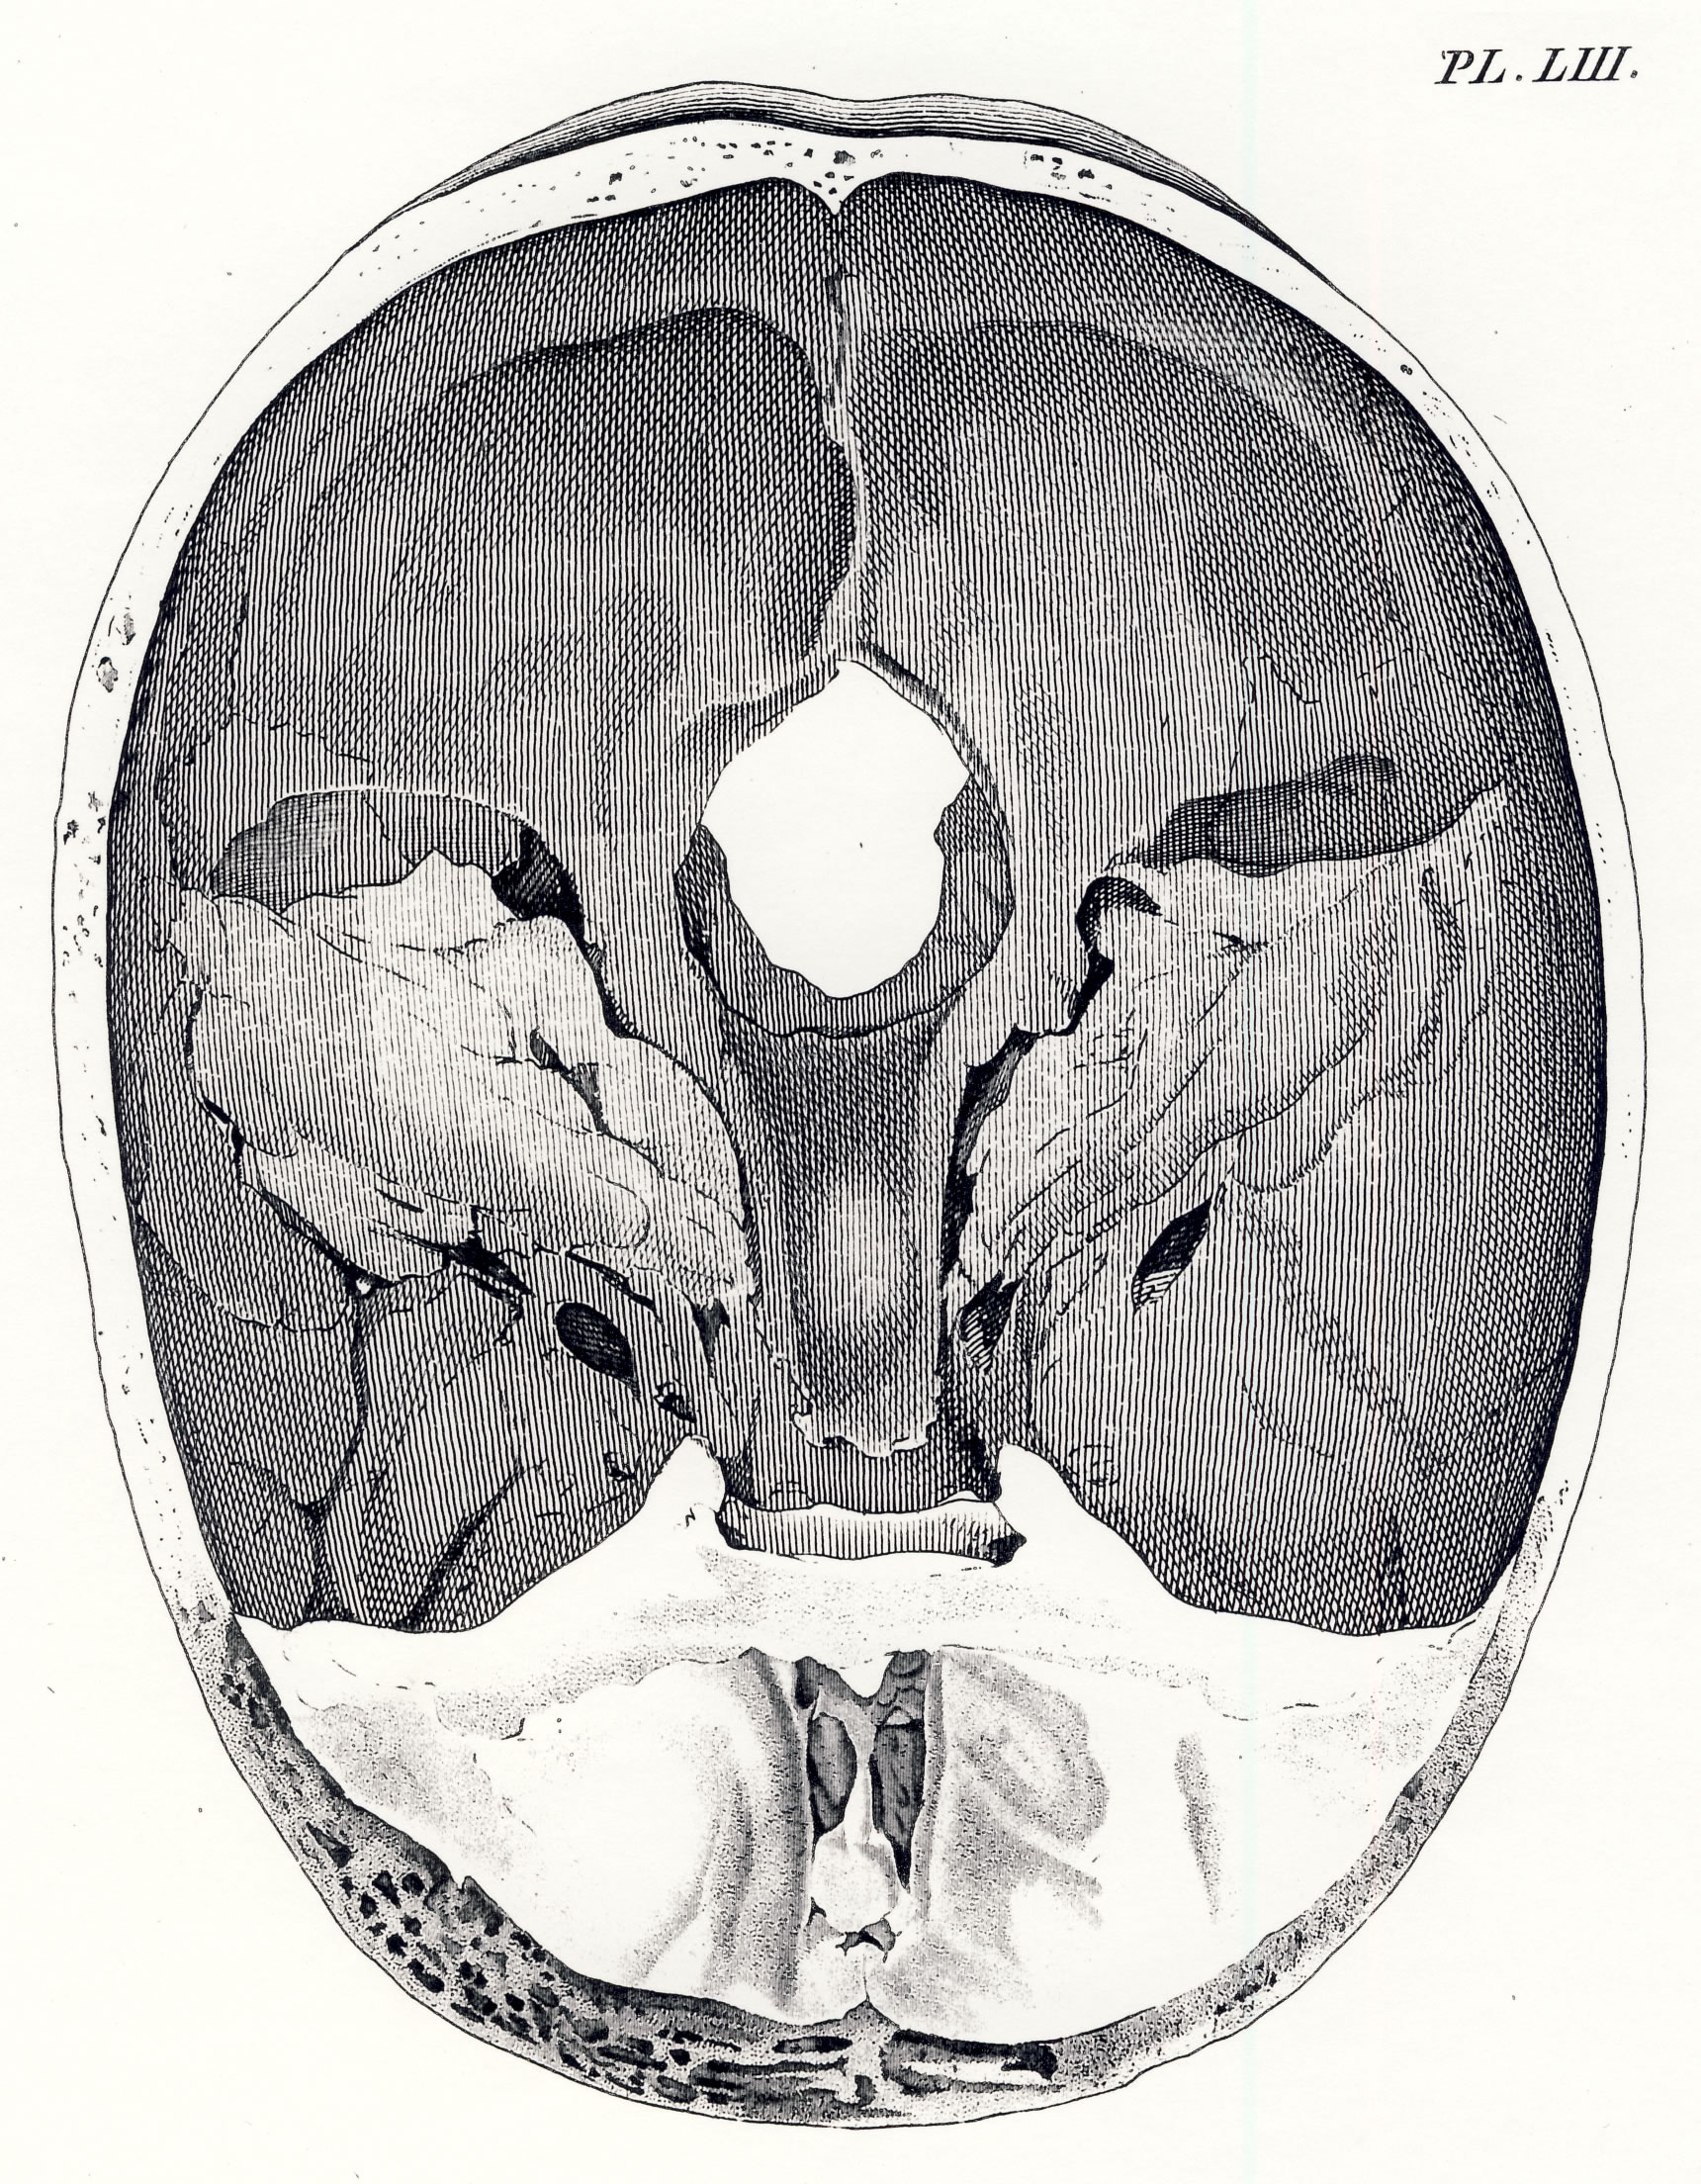

Gall, F. J. (1818). Anatomie et physiologie du système nerveux en général, et du cerveau en particulier, Avec des observations sur la possibilité de reconnoître plusieurs dispositions intellectuelles et morales de l´homme et des animaux, par la configuration de leurs têtes.

Librairie Grecque-Latine-Allemande, Vol. 3, I-XXXV u. 1-379 100 planches.